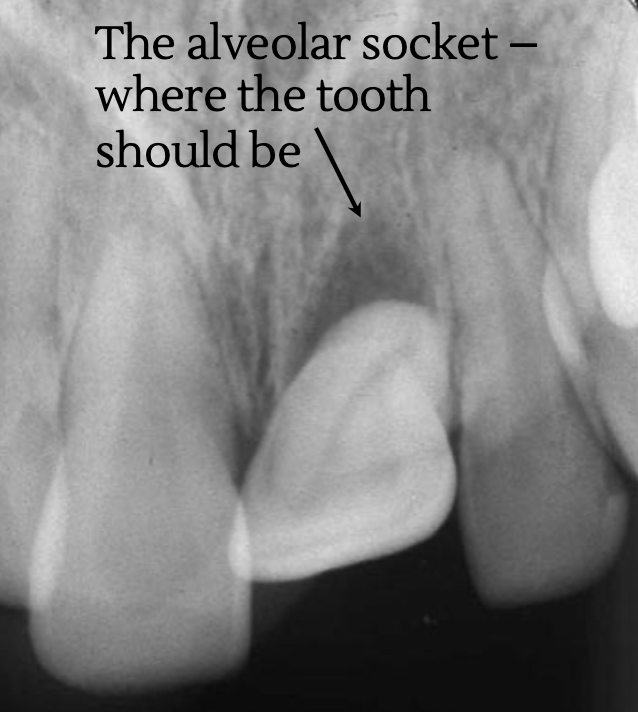

avulsion → tooth completely leaves socket

can mimic appearance of a periapical lesion, but crown appears supererupted

questionable prognosis → depends on how soon tooth is repositioned into socket